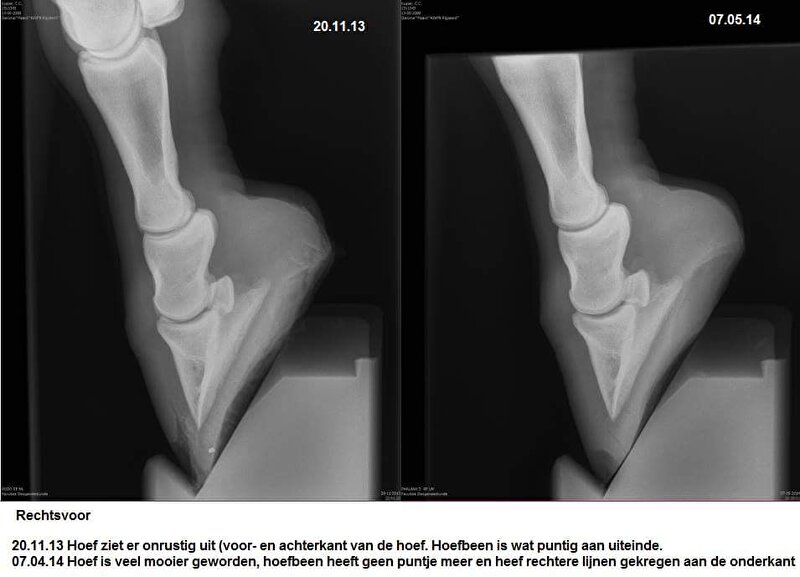

Hier nog wel wat foto's van haar herstel:

Cardy @ [BEH] White Line Disease.. al 12 weken uit de running. Ervaring?